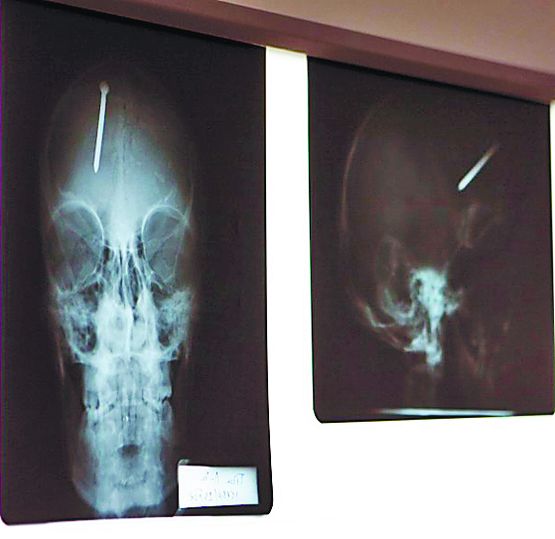

Culmea nebuniei este că individul, fost puşcăriaş, a mai încercat să-şi înfigă un cui în craniu şi săptămâna trecută. Norocul lui a fost că atunci nitul a intrat doar un centimetru în cap.

Perseverent, însă, de data aceasta a reuşit să-l introducă pe tot. Sibianul a povestit medicilor că prietenii lui râdeau de el şi a hotărât să le demonstreze ce a învăţat la închisoare. S-a uitat pe jos, a găsit un cui ruginit şi l-a bătut cu o piatră în propria frunte.

Medicul Vicenţiu Săcelean, cel care l-a operat pe individ, susţine că acesta a venit la Urgenţă pe propriile picioare. „Operaţia a durat aproximativ două ore şi a fost dificilă, pentru că dacă şi-ar fi bătut cuiul cu doi centimetri mai în dreapta, i-ar fi atins o arteră importantă şi probabil n-ar fi supravieţuit”, a povestit medicul. Acum, bărbatul se află în reanimare, iar medicii îl ţin sub observaţie, pentru că există riscul să apară complicaţii din cauza unor eventuale infecţii.